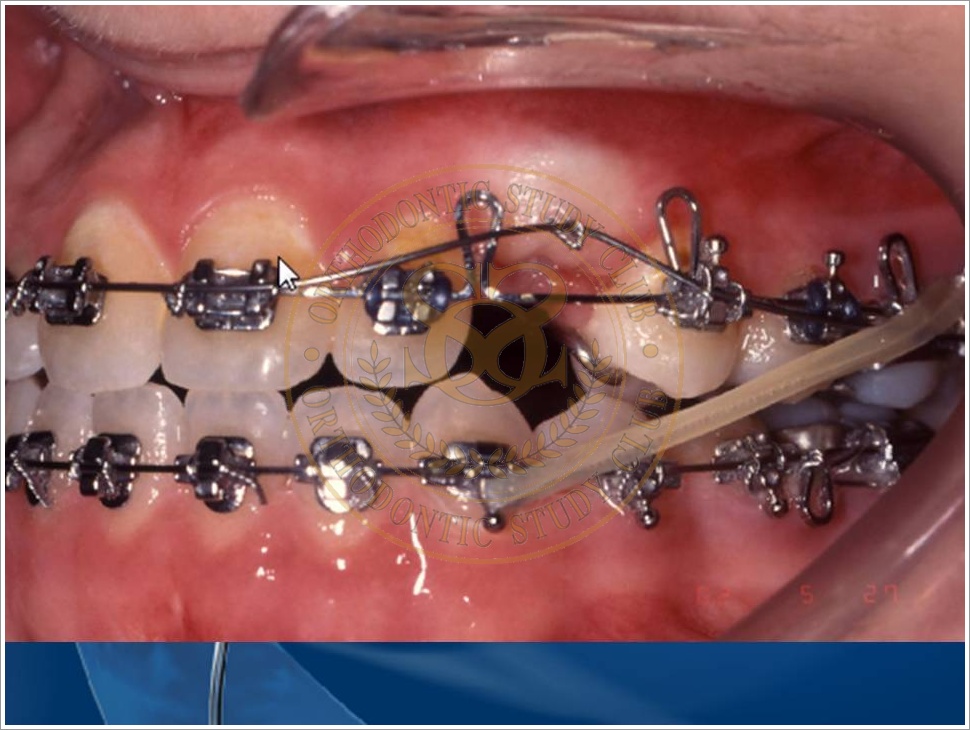

Treatment of Pseudo Class III (Class I Molar Relationship) and management of the embedded maxillary canine (Pt. Miss J.I.)